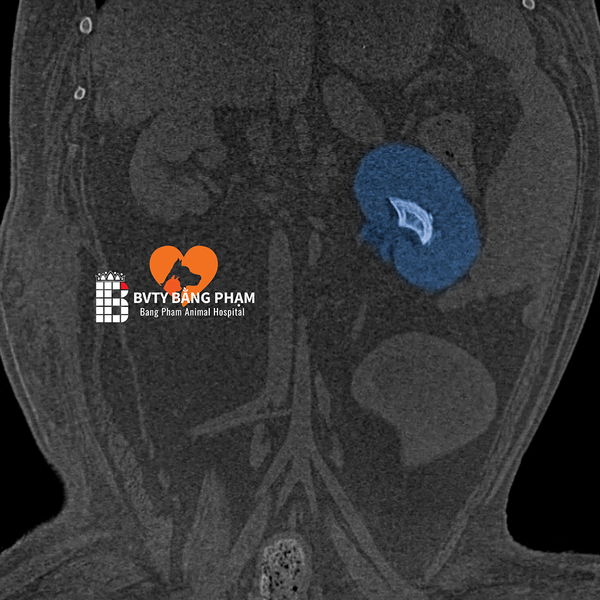

🔍7. Hình Ảnh Thực Tế – Kết Quả Sau Khi Chụp

Hình ảnh CT thể hiện chi tiết từng lớp cấu trúc trong cơ thể, giúp bác sĩ:

- Xác định chính xác vị trí khối u, ổ áp xe, hoặc chấn thương sâu.

- Lên kế hoạch phẫu thuật hoặc điều trị nội khoa chính xác.